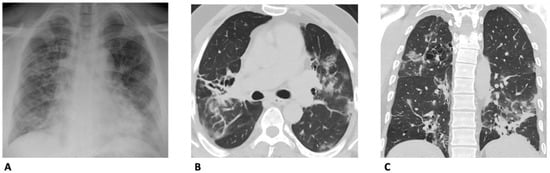

3. Chest X-ray (CXR)

4. Computed Tomography (CT)